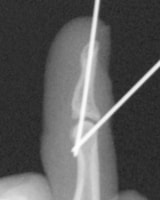

末節骨裂離骨折の経皮ピンニング

槌指とは木槌(マレット)のように変形した指を指す言葉であり、これには、末節骨の伸筋腱が付着する部位の裂離骨折によっておこるものと、伸筋腱の終止腱の断裂によっておこるものが含まれます。

いずれの場合も、症状はDIP関節の自動伸展障害ですが、放置するとスワンネック変形(白鳥の首様の変形)を生じます。さらに、骨折の場合には早期にDIP関節の変形性関節症を生じる原因となることがあります。

治療は、骨折があれば骨片の整復・固定を行うことで良好な結果が得られます。腱断裂の場合には2ヶ月間の外固定により4割の指に良好な結果が得られますが、6割の指には様々な程度(5〜20°)のDIP関節伸展障害が残存します。結果は、どれだけ早期に固定を開始できたか?と、どれだけしっかりとDIP関節の伸展位固定を維持できたか?にかかっており、ただ単に固定していたら治る、というものではありません。